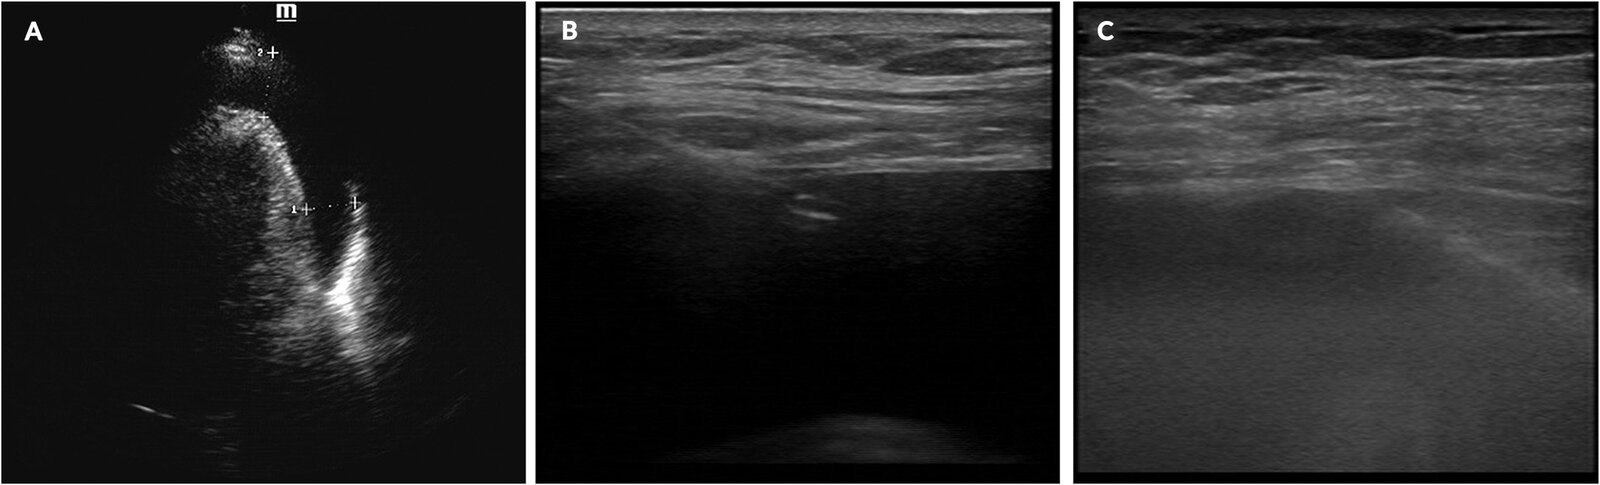

• Guidance with imaging is preferred, e.g., using POCUS, CT, or fluoroscopy.

• Agitated saline can be used to confirm needle positioning within the pericardial space.

There are three main approaches to pericardiocentesis. See β€œFocused cardiac ultrasound” for details on the POCUS technique. [4]